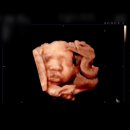

안녕하세요 달이맘입니다👼🏻✨ 강서구 보건소 토요부부 출산준비교실 후기입니다! 신청방법은 서울시 임신•출산정보센터에서 교육신청으로 했어요 ! 선착순 마감되니 일정 확인해서 꼭 하시길 !! ⤵️⤵️⤵️⤵️ 보건소 교육 신청 - 알림·참여 | 서울시 임신·출산 정보센터 페이지 검색 분류 임신준비 임신 출산·육아...

사소한 일상이 곧 행복,(2025-11-20 17:00:00)

안녕하세요 오늘은 지난 주말에 다녀온 강서구 보건소 토요출산 준비교실 후기를 남겨보려고 해요 출산이 아직 남은 것 같으면서도 달력을 보면 또 그렇게 멀지만은 않은 느낌이라, 요즘은 이런 교육 하나하나가 더 소중하게 느껴지는 것 같아요 📌 신청 방법 & 장소 토요출산 준비교실은 서울시 임신·출산 정보...

뽀짝한 일상나눔(2026-01-13 08:10:00)

작년에 임신사실확인서를 발급받은 후 바로 다녀온곳은!! 바로 강서구 보건소인데요. 임신확인서랑 신분증을 들고 방문하시면, 모성검사진행 및 임신축하선물을...올리네요 ^^;;ㅋㅋ 그럼 상세한 후기 하나씩 남겨볼꼐요! :) 공지/새소식 - 보건소소개 - 강서보건소 총 2,824 건 ( 1 / 283 페이지) 조건선택 검색어...

기분좋은 소소한 하루(2026-01-29 15:48:00)

중기에 들어서면서 “철분제는 언제부터 받으라고 했더라?” 하고 찾아보니 임신 17주부터 수령 가능하더라고요. 준비물은 신분증만 있으면 됩니다! 강서구보건소에 들어가서 1층 왼쪽 끝편으로 가면 모성실이 있어요. 처음 방문하시는 분들도 찾기 어렵지 않아요! 따로 번호표는 없었고, 평일 오전에 방문했을 때...

산타•루돌프 엄마의 일기장(2026-01-15 23:35:00)